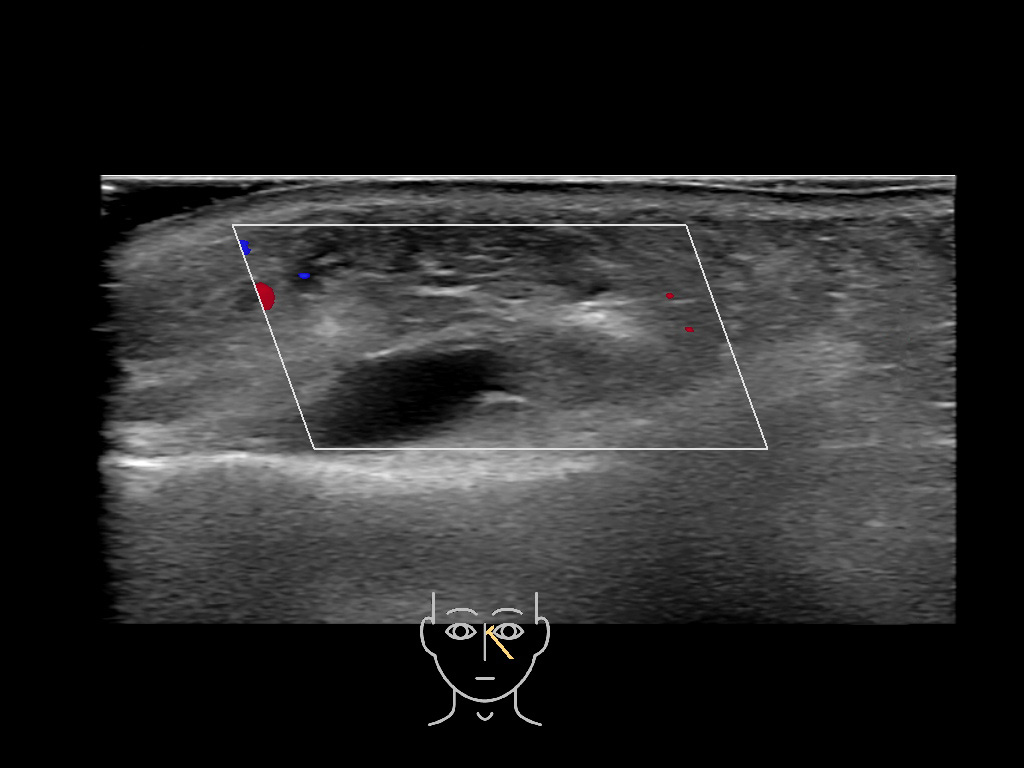

With ultrasound signs of inflammation can be visualized. Edema can be seen as a hyperechoic appearance of the subcutaneous fat, sometimes separated by hypoechoic fluid filled area’s, known as cobblestone appearance. Increased vascularization (hypervascularity) can be seen on colour Doppler. An abscess will appear as a fluid collection appearing as an irregular hypoechoic area with heterogeneous internal echoes and a thickened wall. Posterior acoustic enhancement can be present, and there is vascularity around but not within the mass. Under ultrasound guidance, abscesses can be managed by needle aspirations (18G) under antibiotic cover.

Study the first image to recognize the different layers. If you are sure about the layers, swipe to the second image to view the answer (if applicable).